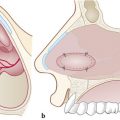

Incisions (Fig. 17‑2b):

Two parallel incisions are made through the floor of the nose; the first should be located at least 5 mm anterior to the anterior border of the septal perforation, and the second incision at least 5 mm posterior to the posterior border of the perforation.

Anterior incision usually starts in the inferior meatus, at the level of the piriform aperture and it is extended medially along the nasal floor until the premaxilla.

Posterior incision runs parallel to the anterior incision but begins at the junction between the soft and hard palate and, if needed, can be extended laterally to the posterior insertion of the inferior turbinate.

Lateral incision connects the two previous cuts (anterior and posterior) along the inferior meatus. For large perforations, the extended version of this flap including the mucosa of the inferior turbinate can be achieved by placing the lateral incision higher in the lateral wall. 4 , 5

Those incisions can be made with an electric scalpel or a cold instrument, depending on the surgeon’s preference. It might be necessary to use sharp scissors to free the flap from the deep fibers at the level of the anterior nasal spine.